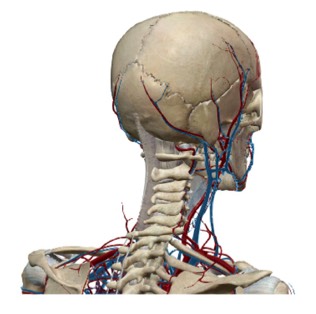

VENA JUGULAR

Ayat diatas merujuk secara langsung kepada salah satu urat yang penting dalam sistem peredaran darah iaitu urat leher atau “jugular vein” yang menjadi sebahagian dari rangkaian vena yang berfungsi membawa darah yang mengandungi kabon dioksida kembali kejantung untuk disegarkan semula dengan oksigen dalam proses pernafasan di paru-paru.

Setelah AlQuran menyentuh URAT VENA, Allah SWT melengkapakan sistem peredaran darah dengan menyentuh satu lagi urat utama iaitu ARTERI yang menjadi sebahagian dari rangkaian utama yang disebut AORTA pada ayat 44-46 dari surah yang ke69 AlHaqqah.

Perkataan “Al-Watin” pada ayat ini telah diterjemahkan kepada beberapa makna yang kesemuanya terjurus pada maksud yang sama iaitu “AORTA”, yang merupakan “nadi kehidupan”. Disini kita dimaklumkan oleh Allah SWT akan fungsinya aorta dan rangkaian arteri yang menjana kehidupan manusia kerana sekiranya terputus rangkaian ini maka kematian akan menyusul hampir dengan serta-merta.

Mari kita teliti bentuk organ Jantung pada gambar sisipan. Kita akan dapati ada tiga cabang pada aorta sejurus selepas meninggalkan jantung. Sekiranya kita bayangkan jantung sebagai pusat rezeki dan peredaran darah sebagai sebuah kenderaan, persimpangan pertama yang akan dilalui oleh kenderaan darah ini ialah bahagian kepala dan juga kedua belah “sayap’ tubuh yang merangkumi bahu dan kedua belah tangan yang disebut dalam istilah anatomy sebagai "UPPER EXTREMITIES"